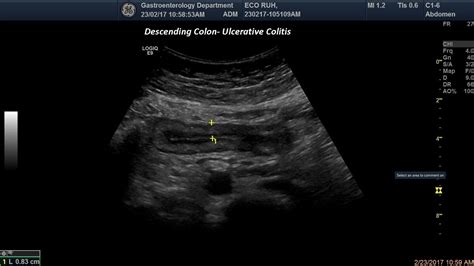

- Inflammatory Bowel Disease (IBD): Conditions like Crohn’s disease and ulcerative colitis are primary causes. Chronic inflammation leads to sustained swelling and tissue changes.

- bowel wall thickening ultrasound

- bowel wall thickening radiology